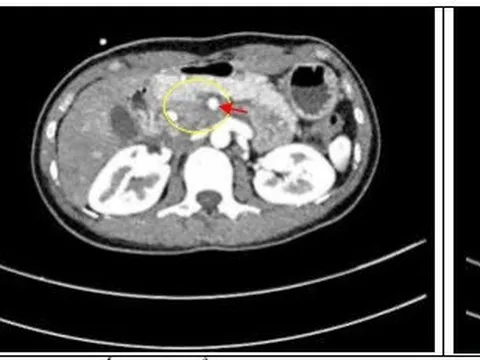

Phương pháp điều trị đem lại hy vọng cho bệnh ung thư đầu tụy giai đoạn tiến triển

(Chinhphu.vn) - Việc áp dụng phối hợp đa mô thức kết hợp điều trị hóa chất tiền phẫu với các kỹ thuật mổ khó và chuyên sâu, các bác sĩ của BV Bạch Mai đã điều trị thành công cho những trường hợp ung thư tụy giai đoạn tiến triển, mang lại hy vọng sống cho người bệnh.